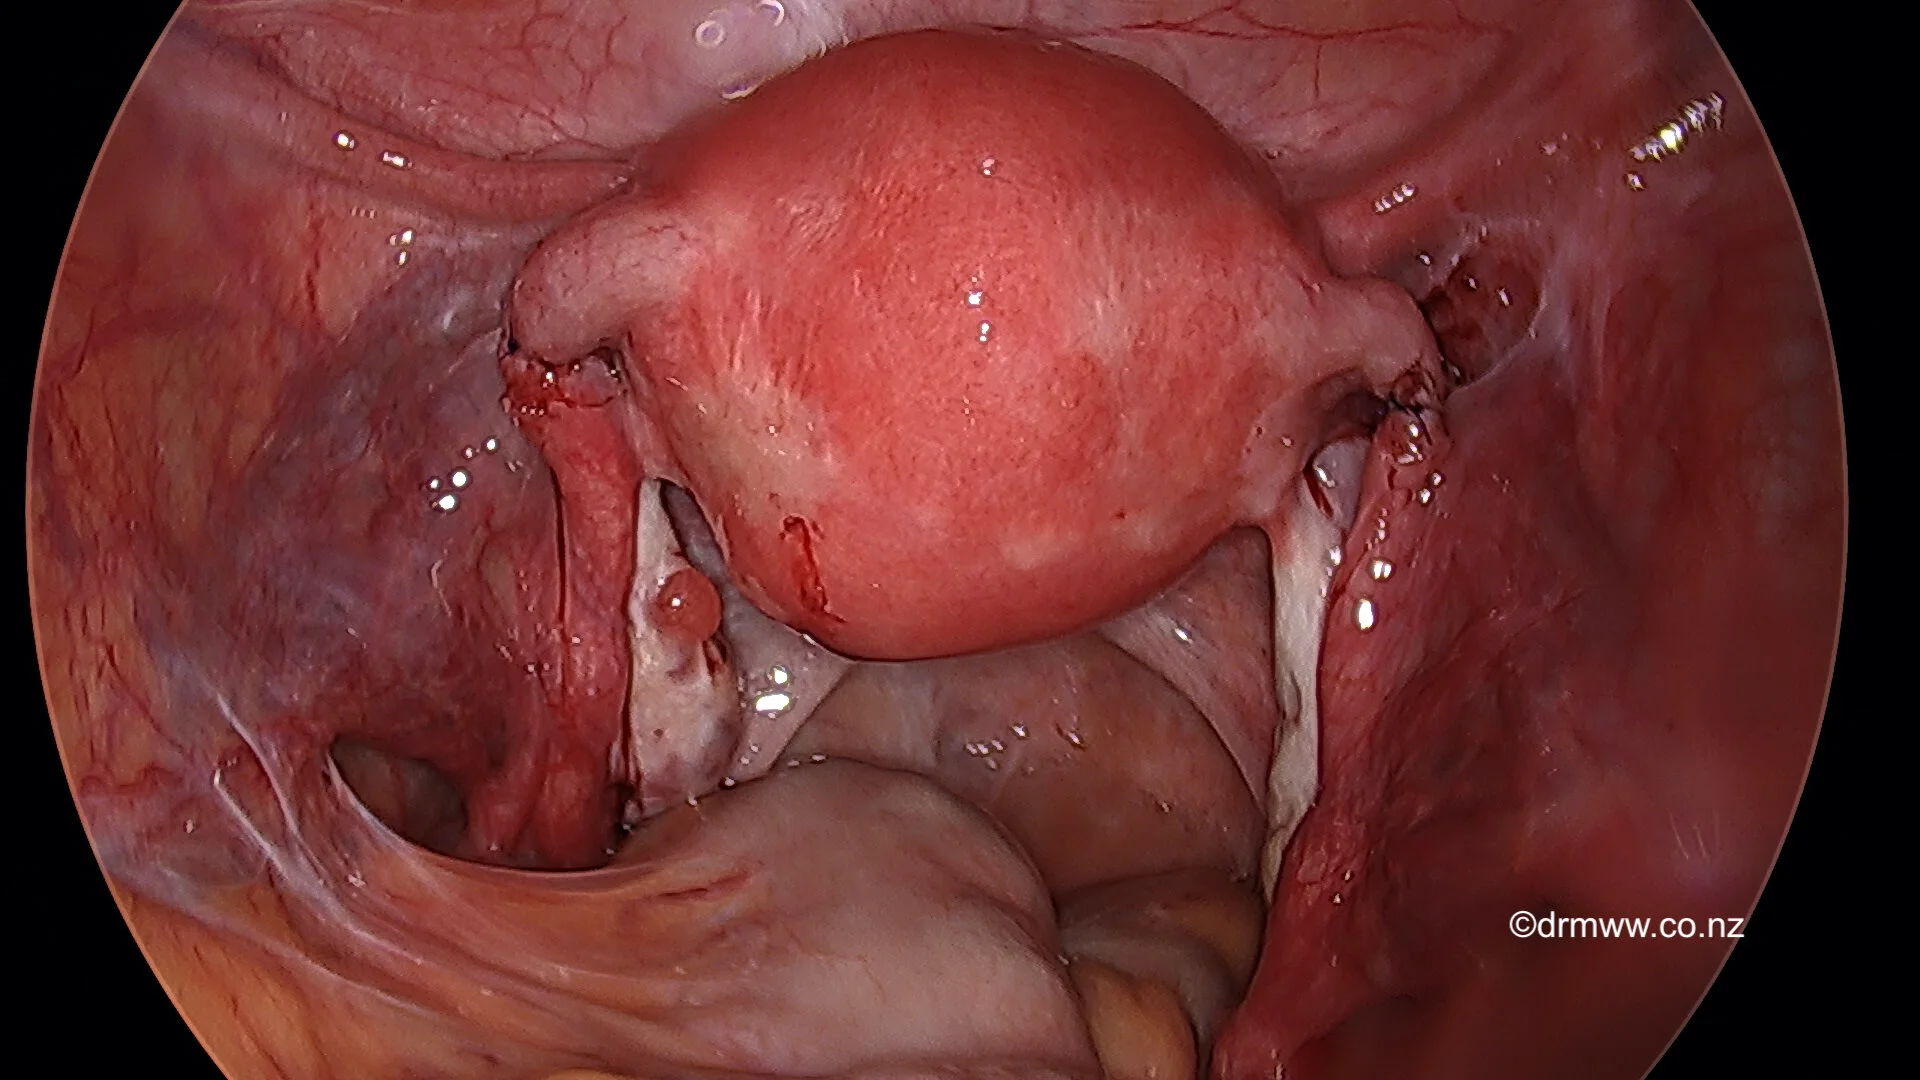

Laparoscopic view of previous tubal ligation (divided Fallopian Tubes)